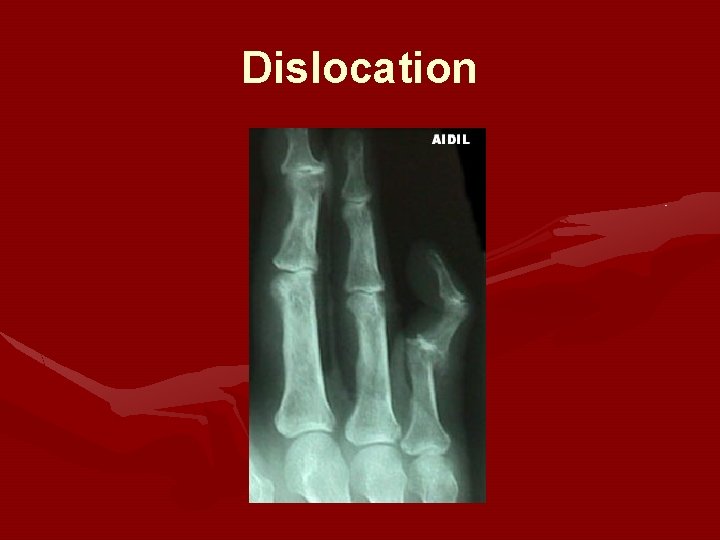

Interphalangeal Dislocation • • Can affect PIP or DIP joint Axial force to the tip of the finger Blow to tip of finger Falling directly on extended finger – May rupture tendon, avulse bone, pinch volar plate

Dislocation

PIP dislocation